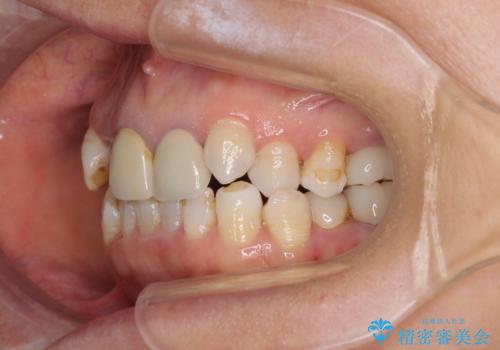

- 全顎的な歯列不正と、銀歯だらけの奥歯を気にして来院された患者様です。

奥歯の銀歯は、セラミッククラウンを装着するには歯の高さが不十分であり、そのままでは矯正治療を行うことが困難であるため、歯冠長延長術を行うこととしました。

また、根管治療の必要な歯がいくつかあるため、歯周外科治療の治癒期間を利用して根管治療を行い、その後インビザラインにて矯正治療を行うこととしました。

矯正治療後にはオールセラミッククラウンにて補綴治療を行うこととしました。